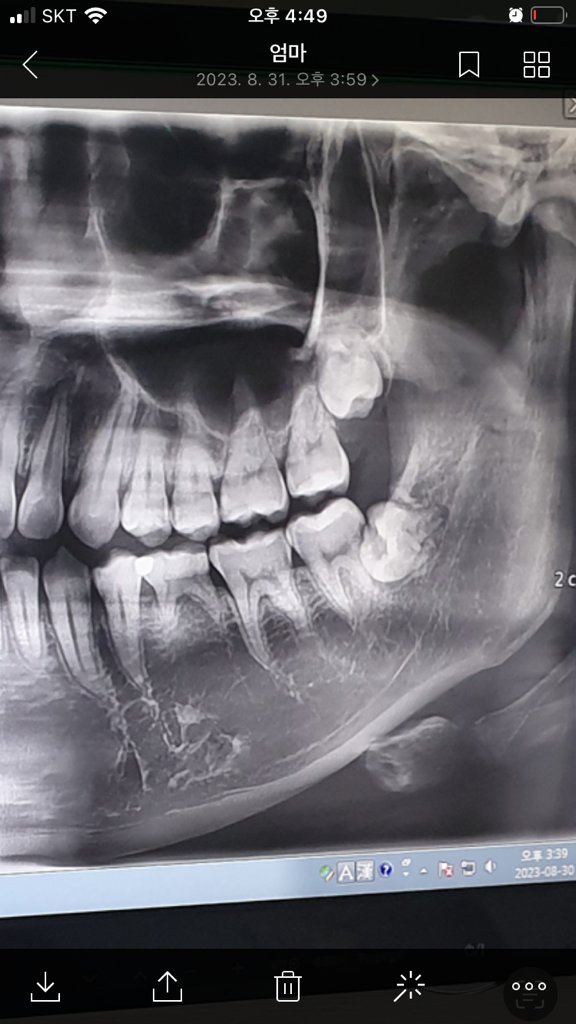

매복 사랑니 발치를 해야할까요

저 사랑니가 아직 잇몸 위로 나오지 않았는데 치과에서 사랑니는 자랐다가 안 자랐다가 해서 좀 기다리면 안아프다는데 씹을 때 하고 입 벌리면 아파서 불편한데 계속 기다리는게 맞을까요? 매복사랑니는 빨리 뽑는게 좋다는걸 봐서요

왼쪽 아래 사랑니는 발치를 하시는게 좋을것같습니다. 사진상에서 보면 사랑니 앞 뒤쪽에 충치가 잇는것처럼 보입니다.

누워있는 매복 사랑니는 방향이 비뚤어져 나오면서 바로 앞 어금니에 걸리는 경우가 많습니다. 현재 각도상 앞의 어금니를 상하게 할수 있기에 빠른시일내에 발치를 권합니다.

매복니 발치는 까다로운 발치로, 매복니 발치 경험이 풍부한 구강외과전문의에게 치료를 받길 권합니다.

1. 아래 사랑니의 경우 완전히 두번째 큰 어금니 그리고 뼈(ramus)에 걸려 있기 때문에 (locking) 더이상 움직이거나 나올 가능성은 적습니다. 위치상 두번째 큰 어금니를 밀고 있어서 치근(뿌리)우식이나 치근흡수의 가능성도 있어 발치가 권장됩니다.

2. 위 사랑니는 아직 좀 더 맹출할 가능성이 있습니다. 위 사랑니 발치를 원한다면 좀 더 내려오고 나서 뽑는 것이 수월하고 덜 위험합니다. 다만, 사랑니가 똑바로 잘 나오면 관리를 잘해서 충치가 안생기게 하고 굳이 뽑지 않아도 됩니다.

3. 왼쪽 유치어금니가 하나 남아있고 하방 영구치(두번째 작은어금니)가 없습니다. 유치를 영구치 대신 계속 쓰셔야 하는데 각별히 관리를 잘해야 합니다.